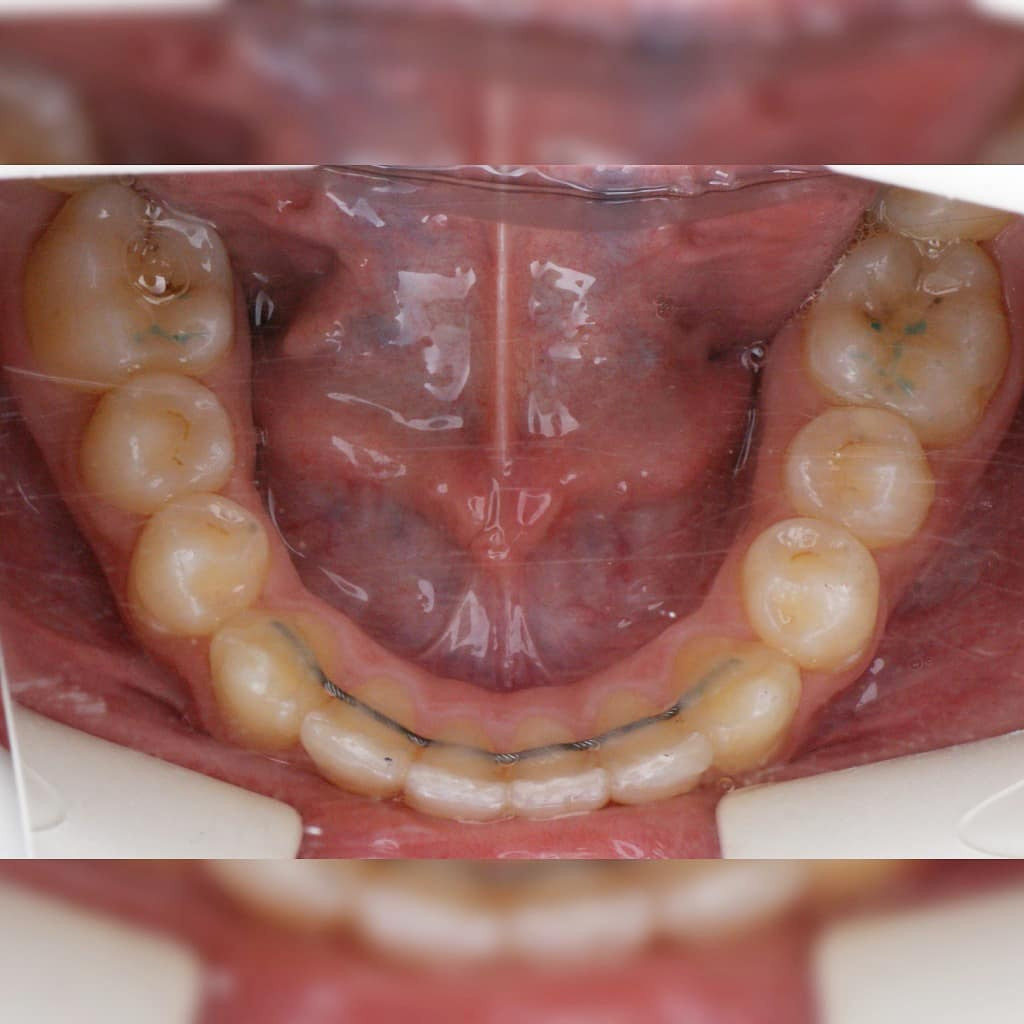

Эта фраза знакома многим ответственным родителям, которые привели на приём к ОРТОДОНТУ своего ребёнка в 5-10 лет, заподозрив проблему или понимая, что места постоянным зубам откровенно не хватает! Горькая правда в том, что брекеты - не волшебное средство от всех проблем, они "расставляют" зубы внутри сформированого объёма челюсти, но никак не влияют на её рост. Родители ждут, а тем временем драгоценное время, когда ребёнок растёт, уходит... Во взрослом возрасте приходится удалять здоровые зубы или прибегать к ортогнатической хирургической операции. 📸 На фото узкая нижняя челюсть, места постоянным зубам нет, боковые резцы прорезываются "вторым рядом".

✅ Помогаем с помощью расширяющей дуги, пружины и зацепных элементов, которые зафиксированы на МОЛОЧНЫЕ зубы